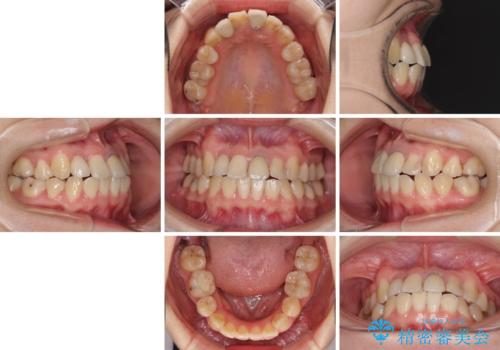

虫歯治療ついでに歯並びの後戻りを改善 インビザラインによる矯正治療

- 奥歯が痛いとのことで来院された患者様です。

上顎親知らず周辺の炎症と、神経組織の失活した歯の炎症による痛みが認められたため、親知らずの抜歯と根管治療を行いました。

根管治療を行った歯はクラウンによる補綴治療が必要となりますが、高校生の頃に行った矯正治療の後戻りも気になるとのことで、補綴治療を行う前に矯正治療を行うこととしました。

後戻りは軽度であり、インビザラインにて歯列を整え、その後にオールセラミッククラウンにて補綴治療を行うこととしました。

ご家庭やお仕事の都合で通院が途絶えた時期があり、治療は長期間となりましたが、無事に終えることができました。